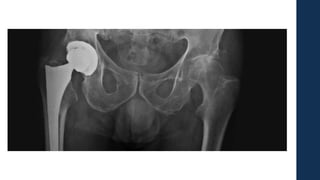

• #14 En esta imagente se puede apreciar los componentes fundamentales: vástago femoral, cabeza femoral , el polietileno (que no se puede ver) y la copa acetabular en un cadera derecha. Para las protesis totales al igual que las parciales tenemos protesis cementadas y no cementadas.

• #55 Aca se ve la imagen radiografia postoperatoria de una protesis convenciónal y la derecha una protesis de revion con vastagos mas largos y con el sistema de bisagra